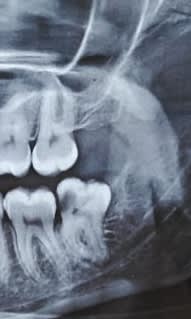

Je devrais faire l'extraction d'une 38 enclavée. En faisant l'analyse de la radio pré opératoire, j'ai des doutes sur la meilleure technique pour l'extraction.. Devrais commencer par enlever tout l'angle distal et essayer de la faire sortir par la suite en entier ou devrais je passer directement à une séparation de racines ? Dans les deux cas j'aurais à diminuer le niveau d'os en vestibulaire..

La base:il faut toujours essayer de mobiliser la dent avec un élévateur avant de séparer tes racines.

Fait ensuite ta résection osseuse en distal et vestibulaire.

Reprend ton élévateur pour travailler au niveau du ligament.

Prend ton davier et fait des mouvement circulaire et non en vestibulaire et lingual sinon tu vas casser ta racine mésiale qui est courbée.

Ensuite si tu n'y arrives pas,tu sépares tes 2 racines et tu les enlèves à l'élévateur.

Lambeau classique

Alveo vestibulaire jusqu'à la furcation et distale

et zou mobilisation.

Si ça sort pas séparation fraise fissure

évidemment examen 3 D pour l'apex ( nerf dentaire...) qui donnera en plus des info pour la suite...